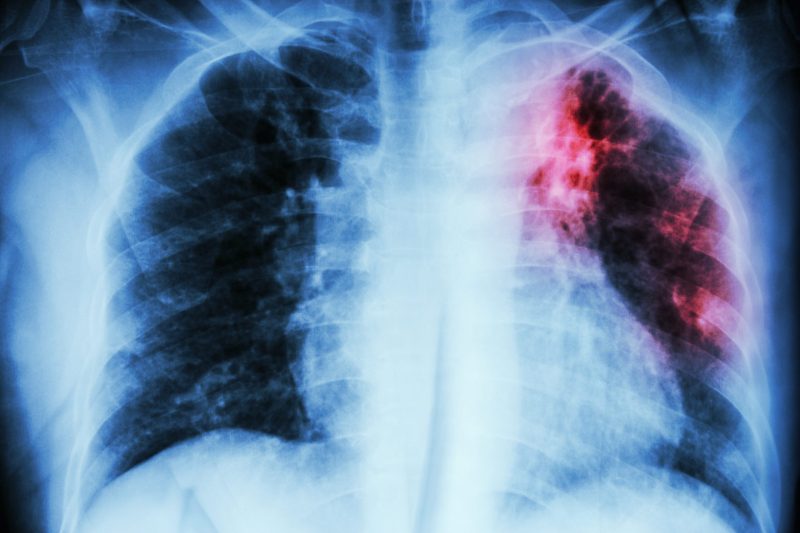

टीबी को ट्यूबरकुलोसिस भी कहते हैं। यह शरीर के विभिन्न अंगों को प्रभावित कर सकता है। हालांकि, फेफड़ों में होने वाला टीबी सबसे आम प्रकार का होता है। कोरोना की तरह फेफड़ों में होने वाला टीबी भी खांसी और छींक के द्वारा एक से दूसरे व्यक्ति में फैल सकता है।ट्यूबरकुलोसिस का खतरा उन लोगों को सबसे अधिक होता है जो जिन्हें पहले से कोई बड़ी बीमारी जैसे कि एड्स या डायबिटीज आदि होती है। साथ ही, जिनकी इम्युनिटी कमजोर होती है उन्हें भी इस बीमारी का खतरा अधिक होता है।